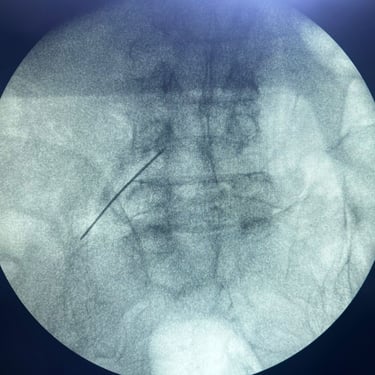

La lumbalgia crónica es una causa frecuente de dolor e incapacidad en el adulto mayor, generalmente asociada a degeneración discal, artrosis facetaria o compresión nerviosa. Cuando el dolor persiste pese al tratamiento convencional, se recurre al bloqueo lumbar selectivo, un procedimiento mínimamente invasivo que consiste en inyectar anestésico y antiinflamatorio alrededor de la raíz nerviosa afectada. Este tratamiento permite identificar el origen del dolor y aliviarlo de manera rápida y efectiva, mejorando la movilidad y calidad de vida del paciente. Es una alternativa segura, ambulatoria y con excelentes resultados en el manejo del dolor lumbar crónico.